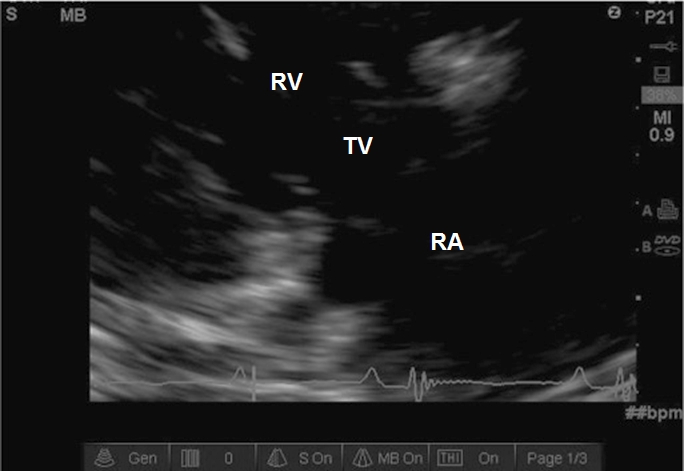

Case 7-6. Right Ventricular Inflow View

Video 7-6A. The anterior tricuspid leaflet is morphologically normal, but the septal leaflet is obscured by an echogenic focus. It does not have the appearance of a vegetation or catheter, but instead is an artifact. Artifacts are common and represent a challenge to the examiner both at basic and advanced training level. The key observation here is that the part of the artifact is not moving in synchrony with surrounding structures and has no other reasonable explanation. In addition, it was not visible on any other view.

Video 7-6B. Color Doppler interrogation of the tricuspid valve with what is mild to moderate tricuspid regurgitation (TR), although other views will need to be examined. The directionality of the color jet is ideal for measurement of the trans-valvular velocity gradient, which would allow an estimate of pulmonary artery systolic pressure. The TR jet velocity would need to be measured from other views as well.